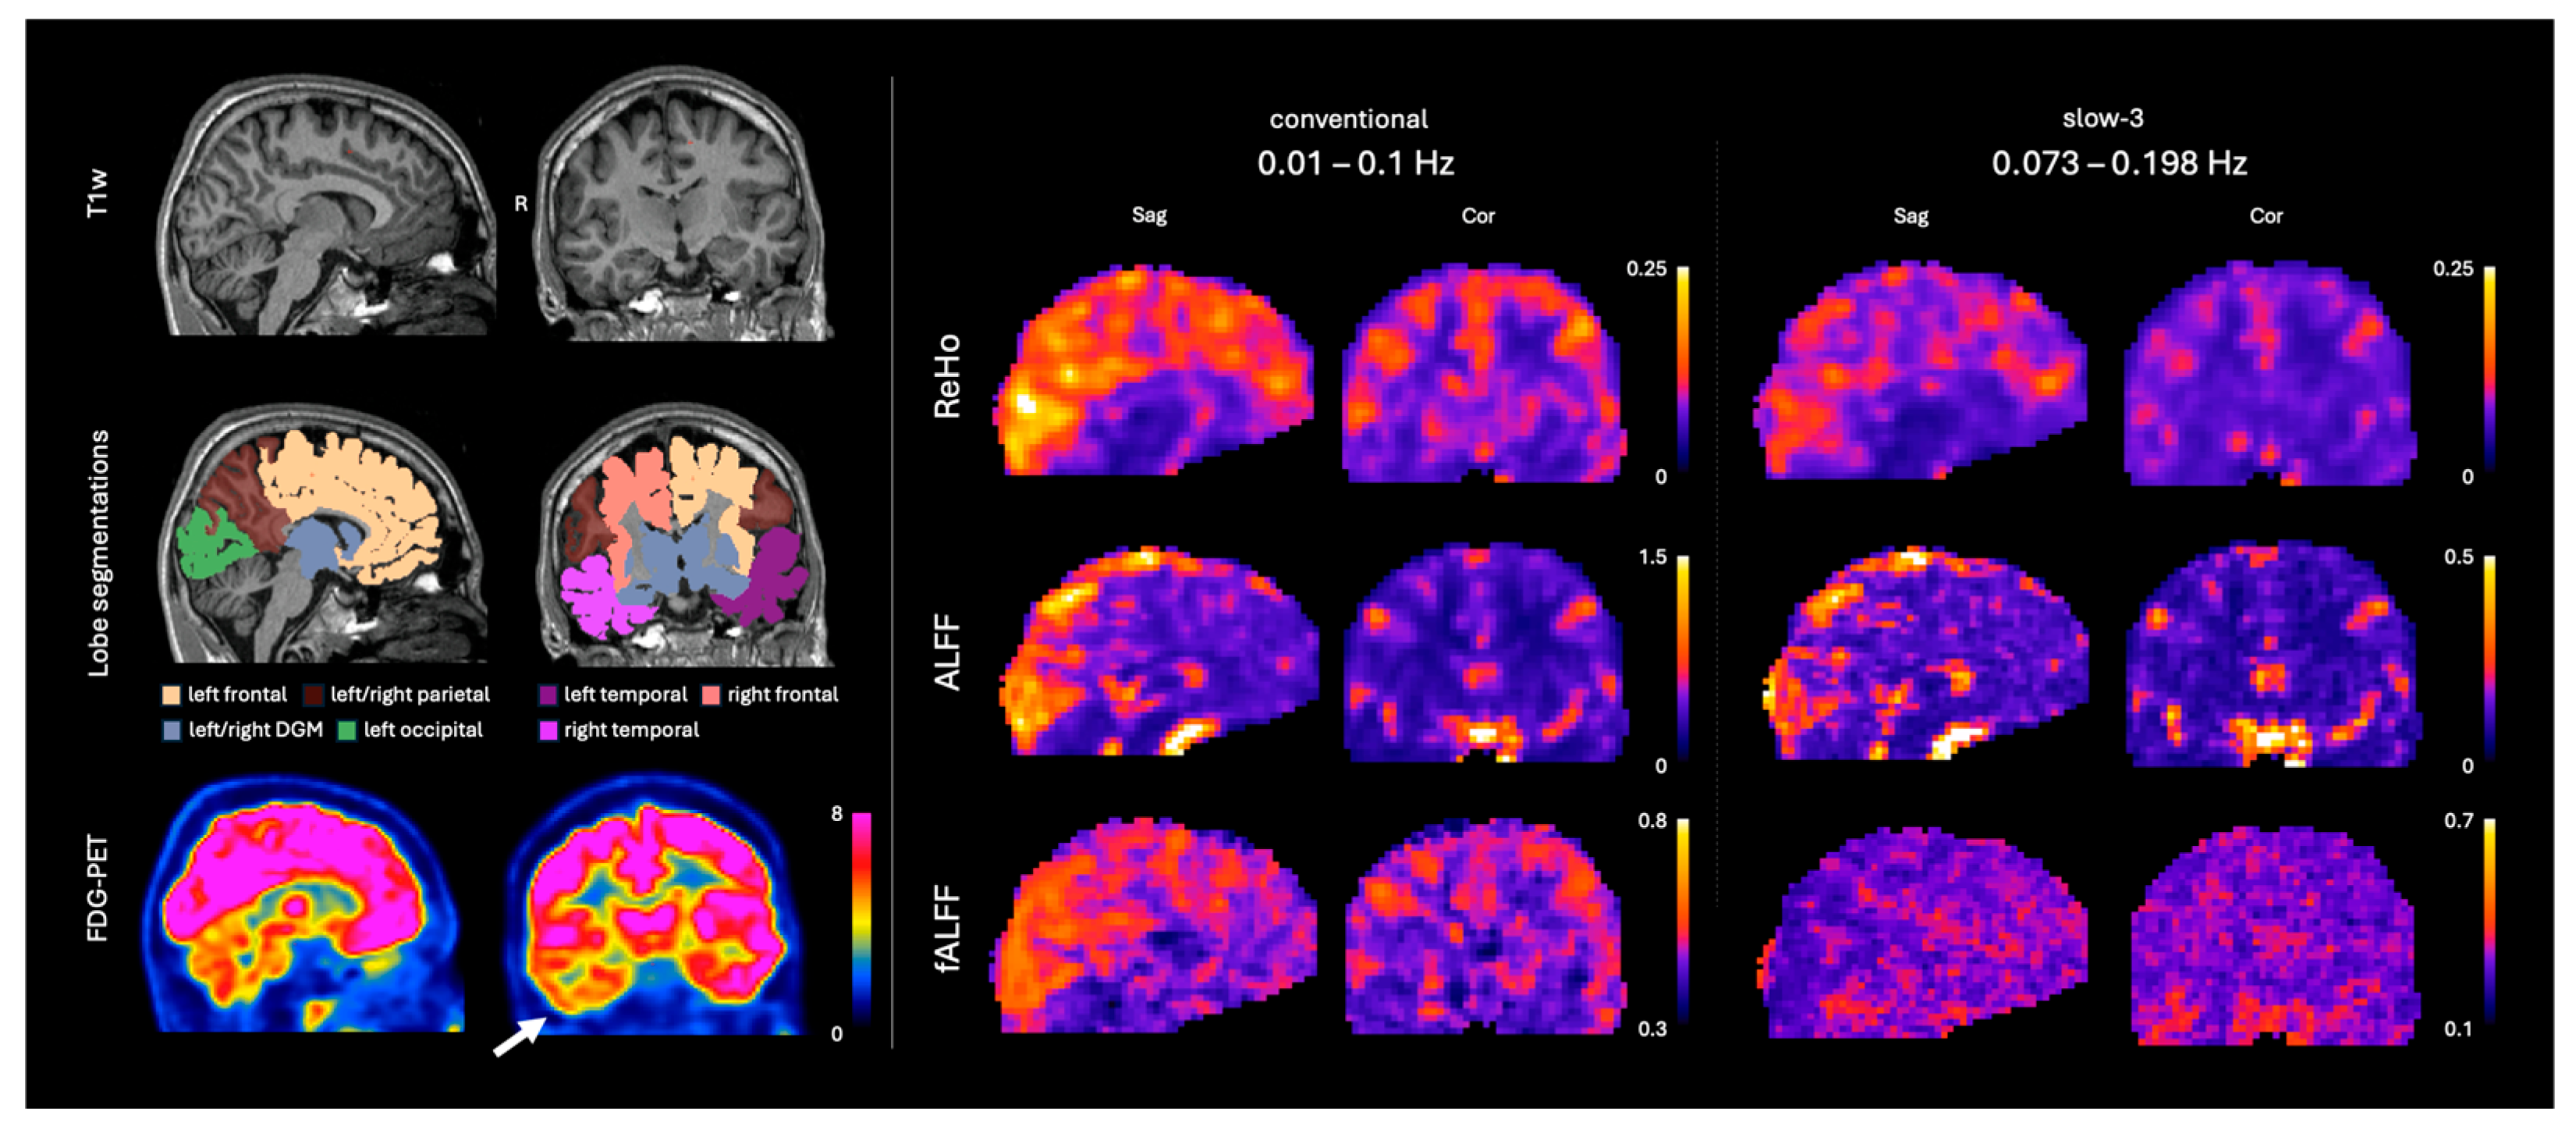

2.3. Resting-State fMRI Processing

| ALFF | Amplitude of low-frequency fluctuations |

| fALFF | Fractional amplitude of low-frequency fluctuations |

| ReHo | Regional homogeneity |